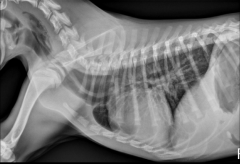

A cat cardiac silhouette radiograph is _____ at the crainal and caudal (compaired to a dog) and ends and appears to have a “_____” shape. The position of the apex is more _____ than a dogs, usually located on or left of midline but sometimes right of midline. In older cats, the cardiac silhouette is more ______ in position.

thinner

lemon

vairable

horizontal (more parallel with the sternum)

In cats, the width of the cardiac silhouette on a lateral radiograph is ___ intercoastal (b/t ribs) spaces. Width on lateral rad is ____ the width of the thoracic cavity.

2

1/2 - a dog is 2/3 the width of the thoracic cavity.

How does the caudal trachea differ in the cardiac silhouette of a cat vs. a dog?

Cat tracheas DO NOT bend ventrally at the heart base.

Dog traches DO curve slightly ventral tat the heart base